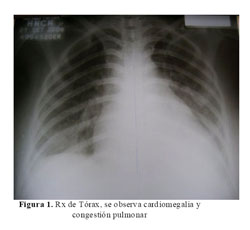

La Rx del tórax mostró cardiomegalia masiva y congestión pulmonar (Figura 1). En la tomografía cerebral se evidenció una hipodensidad en áreas frontales y parietales derechas a nivel cortical y subcortical con transformación hemorrágica (Figura 2). La ecocardiografia era muy similar a la previa, con dilatación e hipocinesia global y fracción de eyección de 25% (Figura 3).